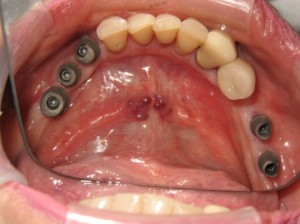

sage-dental-before-1